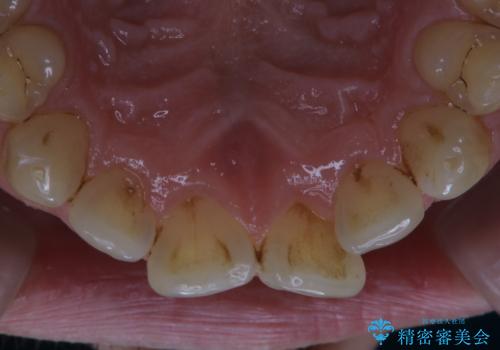

細かいステインをPMTCでOFF

- 歯ブラシをしてもとれないステインが気になるとのことで来院されました。PMTC60分コースを行いました。

PMTCは、歯に付着した汚れを除去していくため、着色が気になる場合にも行うことができます。ご自身でのセルフケアだけで着色を落とそうとすると、逆に歯を傷つけてしまったり、精密に汚れを除去できないこともあります。また、日常生活で着色しやすい飲食物を避けたりすることはストレスに感じてしまったり、あまり現実的ではありません。

毎日丁寧に歯磨きをしていても、日常生活での飲食物などにより着色してしまうことはあります。PMTCでは、歯の表面の凸凹にミネラルを補給して、ツルツルの表面に仕上げます